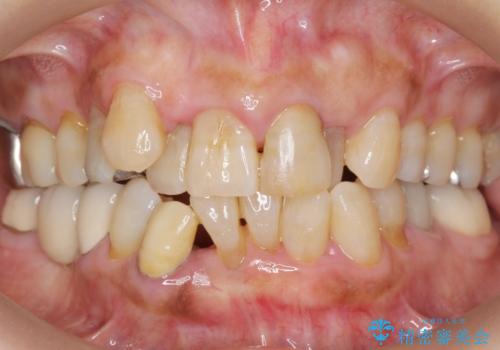

親知らずの移植 4年半経過症例 70代女性

- 親知らずの移植治療から4年半経過した患者様です。

他の歯の治療をご希望され、数年ぶりに来院して下さいました。

移植した親知らずは全く問題ないそうで、「まるで自分の歯のようです。本当にすごい技術ですね。」とおっしゃって下さいました。

歯肉の腫脹や退縮、動揺も認められませんでした。